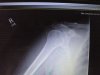

This is not a bike injury. I put my right thumb and index finger into a table saw blade. I’m not riding for a couple of weeks. This really SUCKS.